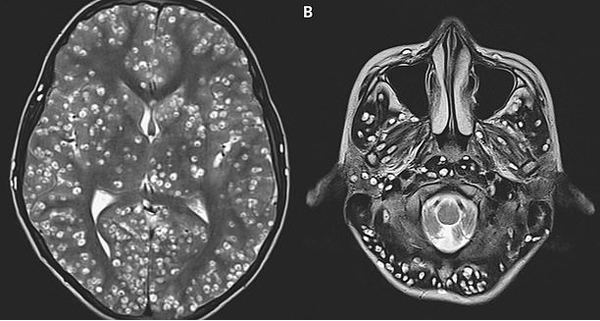

Kết quả chụp cộng hưởng từ trên bệnh nhân rất bất ngờ, bác sĩ phát hiện vô số u nang sán lợn trong vỏ não - vùng chịu trách nhiệm về suy nghĩ, trí nhớ, tri giác.

Các tổn thương tương tự cũng được phát hiện trong thân não - vùng đảm trách chức năng liên lạc giữa não và các phần còn lại của cơ thể; trong tiểu não - khu vực điều phối nhận thức và ngôn ngữ, ý niệm về thời gian và sự chuẩn xác.